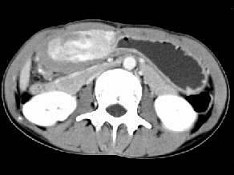

根据所提供的图像,最可能的诊断为()

• A.胃淋巴瘤

• B.胃癌

• C.胃炎性病变

• D.胃平滑肌瘤

• E.间质瘤